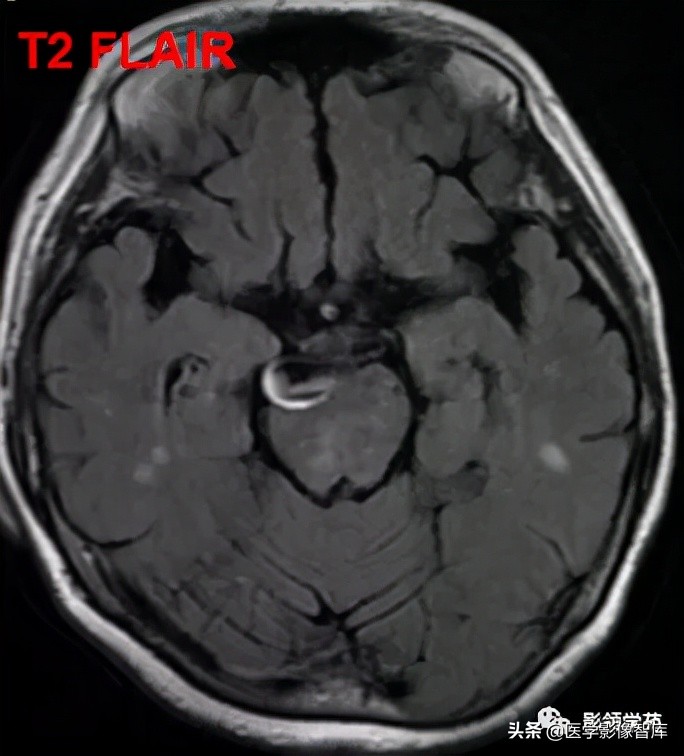

女 72岁,发现糖尿病3年余

鞍上区见一团块状稍高密度影,边界尚清,密度均匀。

鞍上右上方见一类椭圆形流空影。

病灶明显强化(瘤内血栓未强化),边界清楚,与右侧颈内动脉海绵段分界不清。垂体大小、形态未见异常。